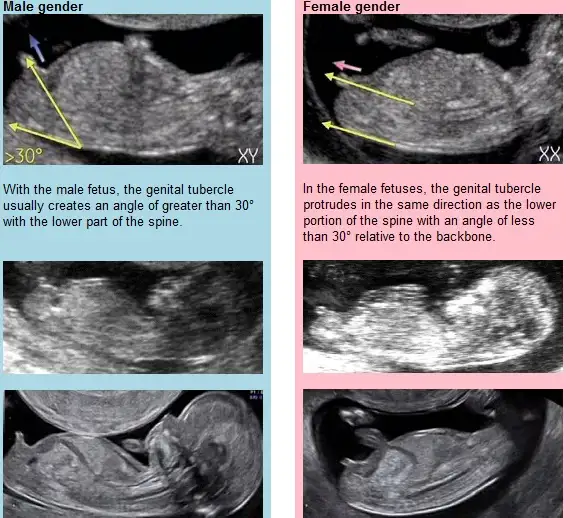

Benziyor canım gerçekten ama erkek olsa 13. haftada söylemez miydi doktor? Erkekler erken gösteriyor sanki kendini.

Sağlıkla gelsinler de önemli değil belli olur bir iki haftaya erken henüzBenziyor canım gerçekten ama erkek olsa 13. haftada söylemez miydi doktor? Erkekler erken gösteriyor sanki kendini.